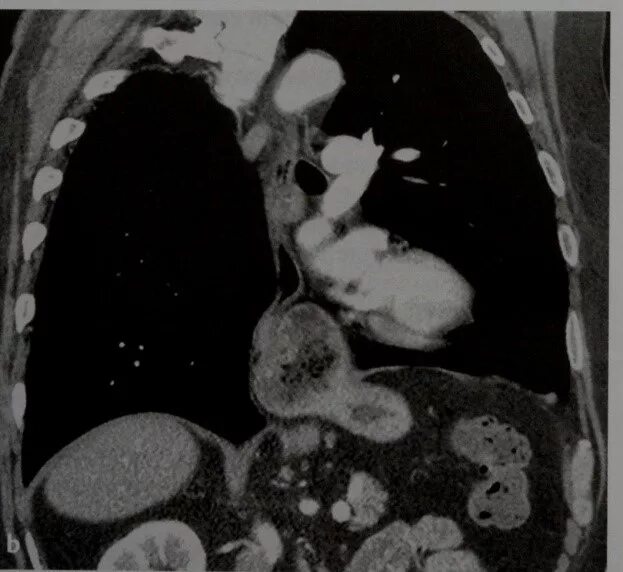

Грыжи на кт